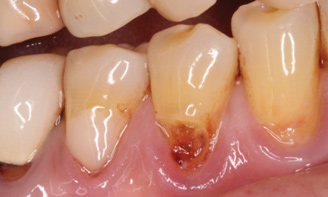

Fig 3. Tooth No. 28 had a Class V filling that failed with recurrent decay (Fig 3). A tuberosity CTG with a 1.5 mm thickness was placed, and after 1 year there was no keloid-like appearance (Fig 4).

Figure 3

Class V fillings are artificial materials that tend to fail at the apical extent and have poor long-term success (Figure 3).1 Conversely, CTGs are natural and attach to the root surface and have high long-term success (Figure 4).1

Dense CT presumably is less susceptible to shrinkage than less-dense CT. One problem with denser CT may be the need for a longer amount of time to blend in with adjacent non-grafted areas. Due to density, a CT graft might never completely blend in and always demonstrate an unesthetic keloid-like appearance. Therefore, with tuberosity tissue, adjusting the tissue thickness prior to placement of the graft is highly clinically relevant. This may be why periodontists have been reluctant to use tuberosity tissue as CT. Palatal tissue has less-dense CT than tuberosity tissue and, therefore, the authors hypothesize and have observed, shrinks more. Because palatal tissue has been the predominant tissue used in CTG, clinicians have become used to the shrinkage associated with the palatal CT and may not realize the need to thin a dense CTG to prevent a keloid-like appearance. Thus, in the past when a tuberosity was used for this purpose, if it was not properly trimmed it would have frequently resulted in an unesthetic keloid-like appearance. The tuberosity CTG should be trimmed to 1 mm to 1.5 mm thick to avoid the need for a future procedure to adjust tissue thickness for esthetics (Figure 3 and Figure 4, Figure 16 and Figure 17).